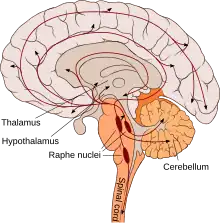

Dans le système nerveux central, les corps cellulaires des neurones sérotoninergiques sont localisés dans les noyaux du raphé du tronc cérébral d'où ils se projettent dans l'ensemble du cerveau et de la moelle spinale. On peut dire[19] que, d'une manière générale : les neurones sérotoninergiques du mésencéphale se projettent rostralement[20] dans les hémisphères cérébraux ; ceux du pont se ramifient dans le tronc cérébral et le cervelet ; et ceux de la moelle allongée vont à la moelle spinale. Les effets de la sérotonine sur les autres neurones peuvent être excitateurs ou inhibiteurs suivant la nature des récepteurs.

Les neurones du raphé dorsal sont connectés à la plupart des régions du système nerveux central (cerveau, tronc cérébral, moelle spinale). La sérotonine est libérée dans des synapses et se lie à des récepteurs localisés sur la membrane de l'élément postsynaptique. Par l'intermédiaire de leurs axones, les neurones du noyau du raphé libèrent la sérotonine sur d'autres neurones du système nerveux central et, en se liant à des récepteurs spécifiques, modulent leurs propriétés électriques. La sérotonine agit en se liant à des récepteurs spécifiques situés dans la membrane des cellules cibles. On connaît au moins 14 gènes codant ces récepteurs sérotoninergiques 5-HT, capables de donner (par épissage alternatif) au moins 30 protéines réceptrices différentes[24].